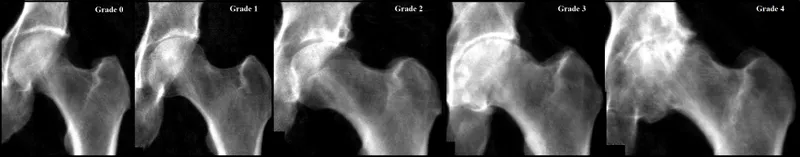

- Kellgren-Lawrence (KL) Grading: Assesses severity (Grade 0-4).

- Grade 2: Definite osteophytes, possible joint space narrowing (JSN).

- Grade 3: Moderate osteophytes, definite JSN, some sclerosis.

- Grade 4: Large osteophytes, severe JSN, marked sclerosis, cysts.

⭐ Earliest sign on X-ray: Osteophytes, often at the femoral head-neck junction or acetabular rim.